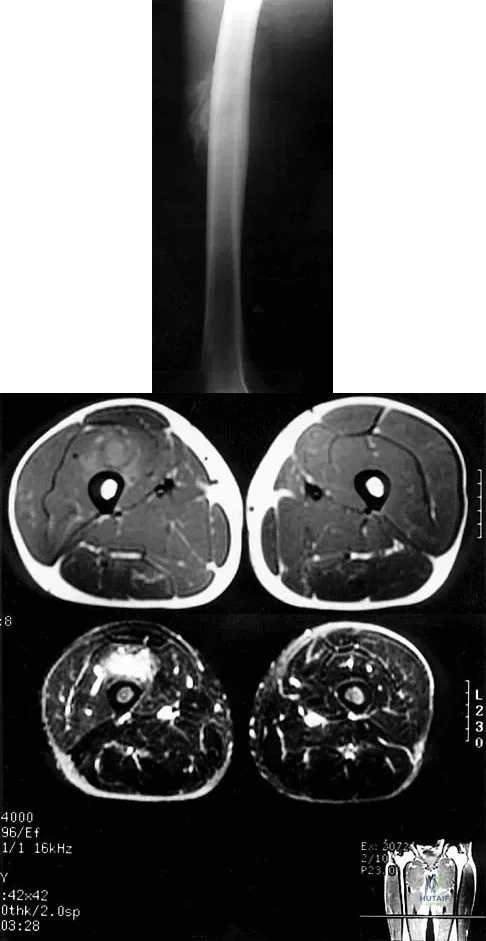

Figures 8a through 8c show the lateral radiograph and T1- and T2-weighted MRI scans of a 14-year-old soccer player who reports aching thigh pain. The next most appropriate step in management should consist of

Explanation:

Although the MRI findings could be misinterpreted as an aggressive soft-tissue process, the periosteal-based ossification on the radiograph in an athlete most likely suggests myositis ossificans. The radiograph should be repeated to see further maturation of the ossification with a typical "zoning" pattern. The zoning pattern is one of peripheral ossification. This is often best seen on a CT scan. King JB: Post-traumatic ectopic calcification in the muscles of athletes: A review. Br J Sports Med 1998;32:287-290.